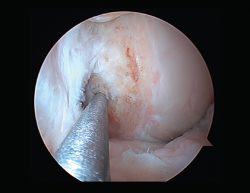

Figura 1. Laxitud en el cajón anterior. Radiología forzada.

Desde el punto de vista clínico, se consideran motivo de revisión quirúrgica aquellos casos en los que exista un desplazamiento anterior comparado con el contralateral mayor de 5 mm, pivot shift de alto grado, dolor, inflamación, sensación subjetiva de inestabilidad y limitación funcional para las actividades de la vida diaria o deportiva(9,10). Algunos autores han rebajado esta cifra a 3 mm con respecto a la rodilla contralateral o 10 mm de desplazamiento absoluto en el plano sagital(11)(Figura 1).